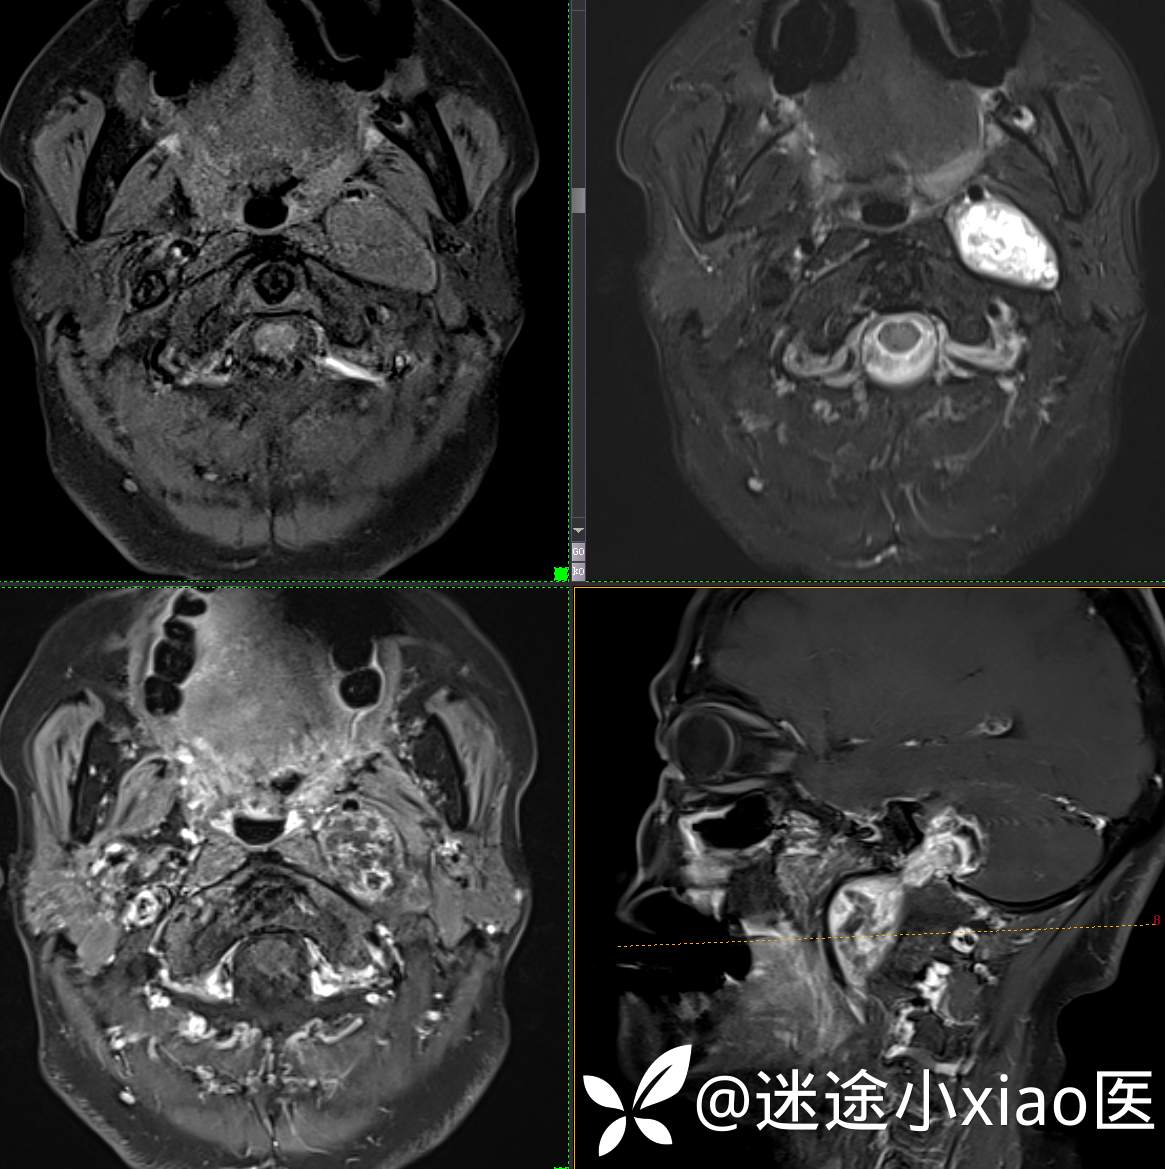

头颈组17:颈静脉孔区占位,副神经节瘤?神经鞘瘤?脑膜瘤?

患者性别:女

患者年龄:57岁

主 诉:  声音嘶哑进食困难伴左侧颌部麻木半年

现病史:  【患者半年前无明显诱因出现声音嘶哑,进食困难,只能进食糊状食物,伴有恶心呕吐,无明显头痛头晕,未加重视。